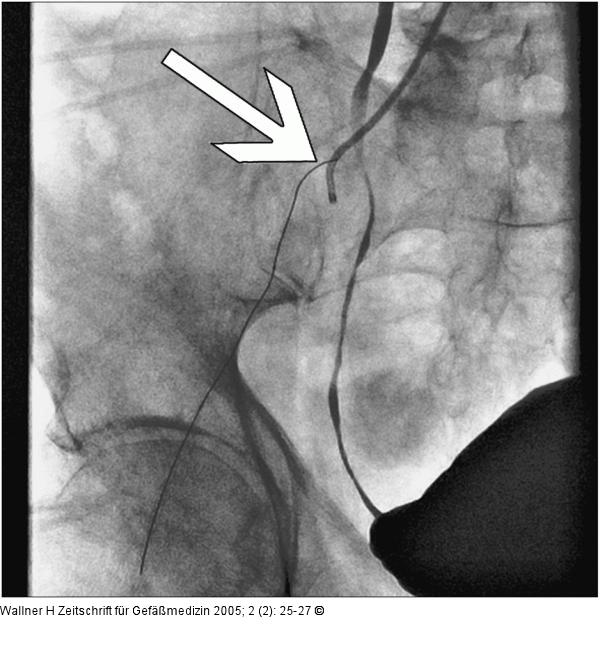

Abbildung 5: A. femoralis communis sin.

Asahi-Draht mit Anschluß in A. femoralis communis sin., liegender IMA-Katheter |